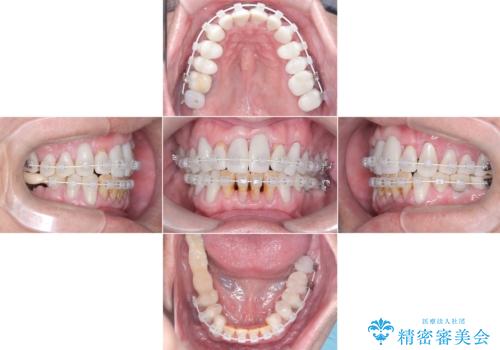

- 強い酸によって歯が広範囲にわたって侵食され、「歯がボロボロになった」と主訴に来院されました。詳細な診査の結果、重度の酸蝕症と診断。失われた歯質や咬み合わせの崩壊が著しいことから、単一の治療では対応が困難と判断し、矯正治療、インプラント治療、セラミック治療を組み合わせた総合的な治療計画を立案しました。矯正治療後に最終的にセラミックを用いて機能性と審美性を回復。患者様と綿密な話し合いを重ね、長期的な口腔内の健康維持を見据えた最適な治療を行いました。

酸蝕症の原因に関しては、医科のほうで解決済みでしたので、失われた機能、審美性の回復のため矯正治療によって歯並びと咬み合わせのバランスを整えセラミックによる修復を行ました。

矯正後、歯肉の形態不良のため、歯周外科を行い連続性を獲得しています。